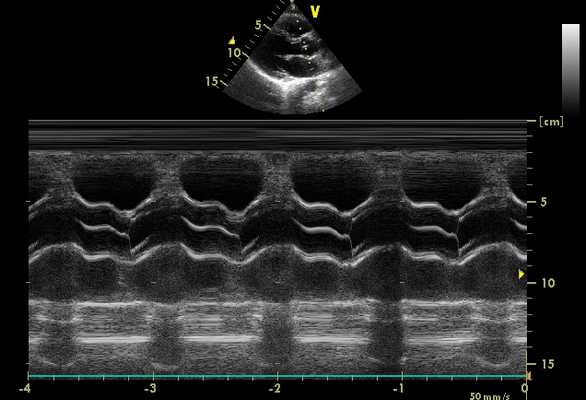

Межжелудочковая перегородка в М-режиме на эхокардиографии

Межжелудочковая перегородка утолщается в систолу в средней части полости левого желудочка. На этом этапе следует произвести измерение и оценку толщины и движения перегородки. Нормальная толщина перегородки должна соответствовать толщине задней стенки левого желудочка и не превышать 1,1 см в диастолу.

Левый желудочек на эхокардиографии

Правильная идентификация левого желудочка может быть сделана, когда видно, что обе его стороны межжелудочковая перегородка сокращается навстречу с задней стенкой сердца. Если перегородка не четко очерчена или кажется, что она плохо двигается, более медиальное размещение датчика вдоль границы грудины с латеральным углом может позволить лучше визуализировать эту структуру. Три слоя задней стенки сердца - эндокард (внутренний слой), миокард (средний слой) и эпикард (внешний слой) - следует идентифицировать отдельно от перикарда. Иногда бывает трудно отделить эпикард от перикарда при небольшой сепарации листков. Миокард на эхокардиографии обычно имеет мелкое рассеивание эхо-сигналов по всему мышечному слою. Эндокард может быть более сложной структурой для регистрации, потому что он отражает слабую эхо-картину. Хорды представляют собой структуры гораздо более плотные, чем эндокард. Обычно они отображаются в систолическом сегменте по передней поверхности эндокарда. Когда желудочек сокращается, эндокардиальная скорость больше, чем скорость сухожильных хорд.